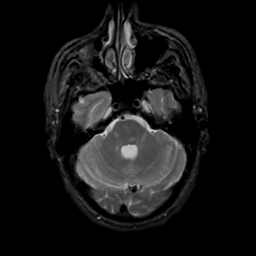

MR Study #8, March 31, 1991 -- Slice #13

[Home][Help][Clinical][Tour 1][Tour 2] Slice 13